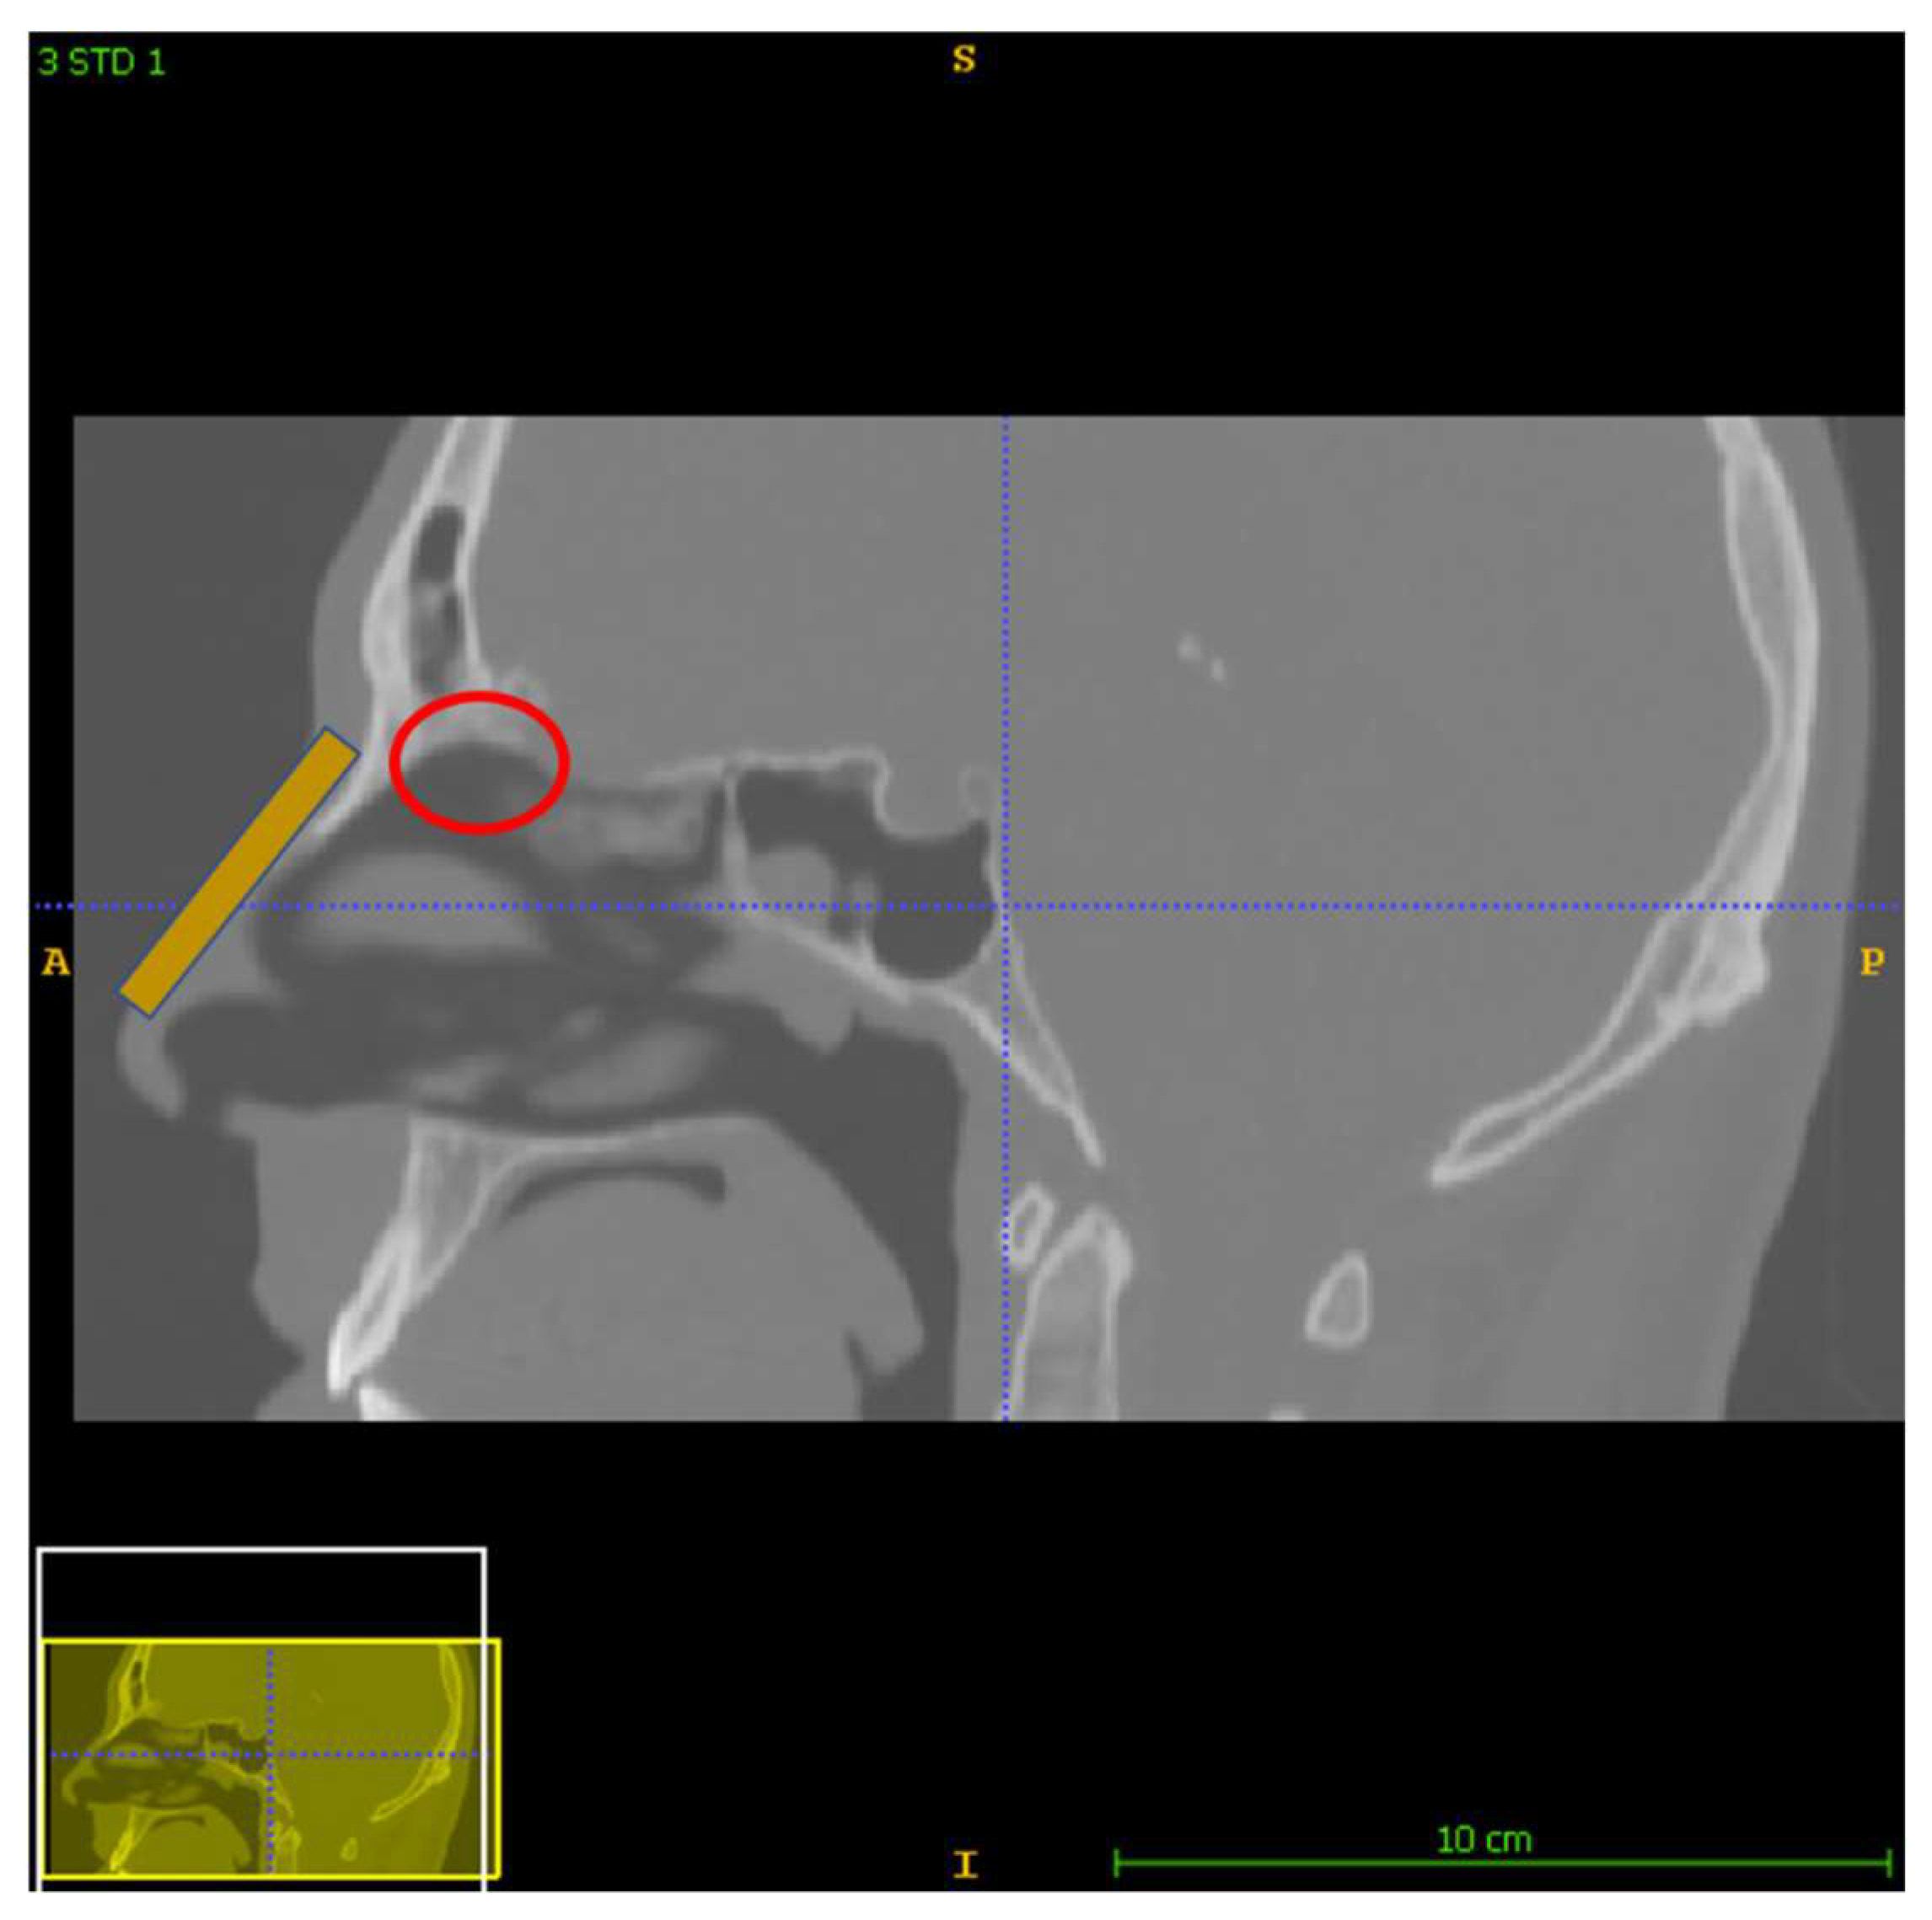

2.1. The Nose and Nasopharynx Model